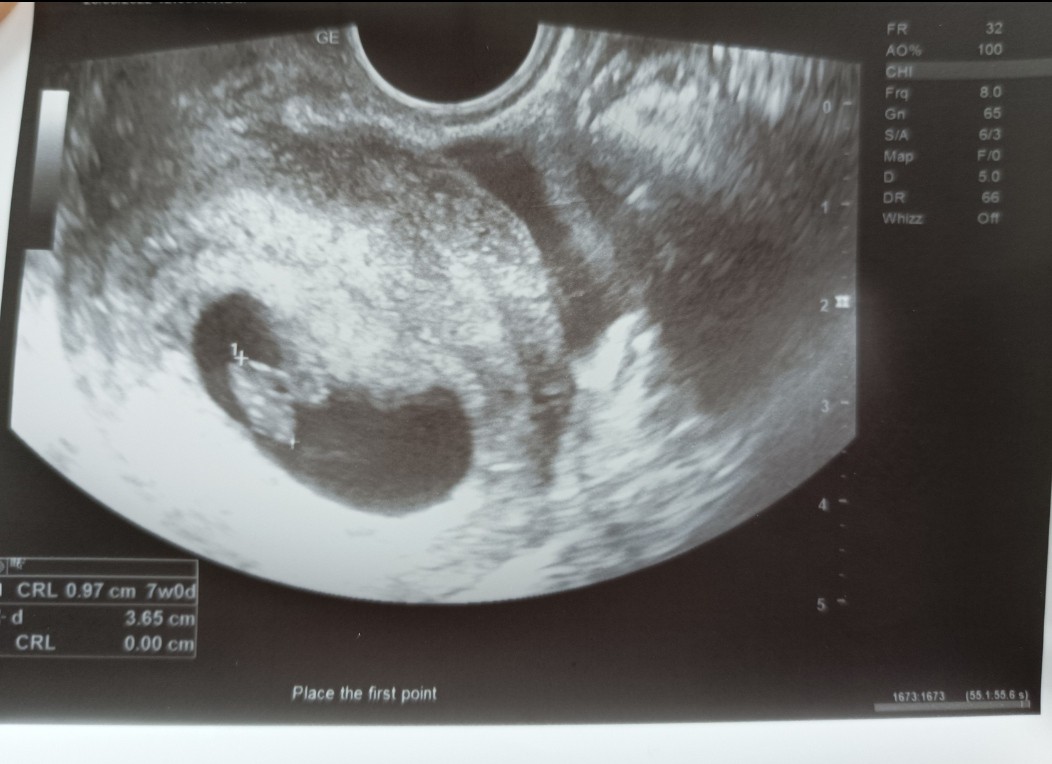

aaaa, ale to lekarz wysyła na takie badanie czy sam to i na wizycie ? Nie wiedziałam ze jest potrzebne na to jakieś skierowanie. Przy synku lekarz zapytał mnie czy chce prenatalne a ja powiedziałam ze nie, bo nawet nie wiedziałam co to, i pomyślałam ze jak dodatkowe to pewnie niepotrzebne. Teraz mam innego lekarza ale nic mi na razie nie mówił o prenatalnych. 🤷🏻‍♀️ na następnej wizycie to będę w 11/12 tc to może wtedy mi coś powie 🤷🏻‍♀️